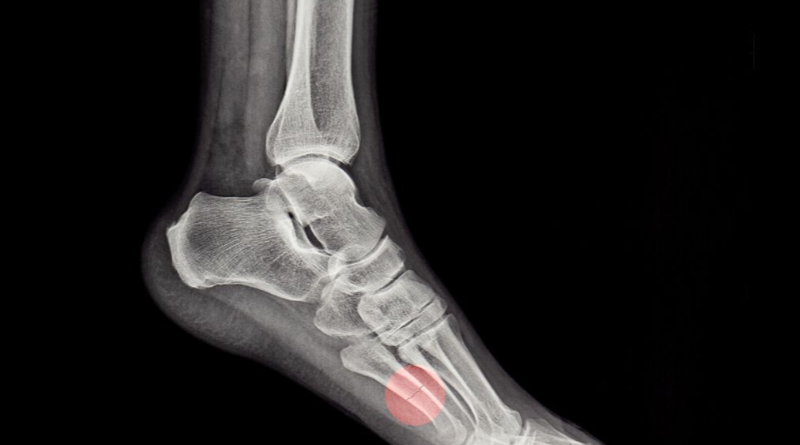

통풍은 혈액내에 요산의 농도가 높아지면서 요산염 결정이 관절과 연골, 힘줄 주위 조직이 침착되는 질병입니다.